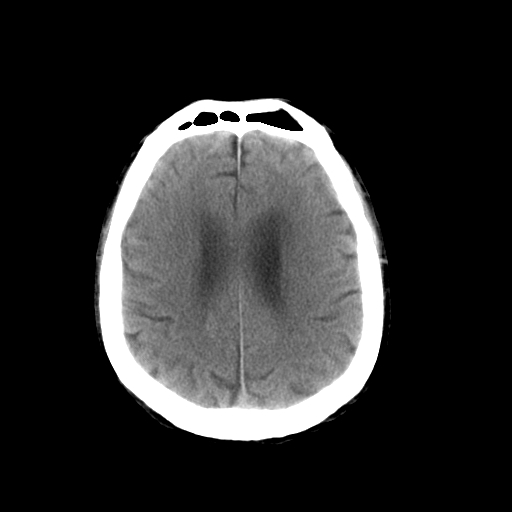

以下是引用dsl555在2008-11-11 18:52:00的发言:[br]四脑室后上方,四叠体池上方可见一小结节状稍高等密度影,比40天略大,建议mri或增强

以下是引用zjzjr在2008-11-12 8:28:00的发言:[br]四脑室后方略高密度影,周围环一低密度水肿带,四脑室受压变形,考虑小脑蚓部血肿吸收期或占位,建议增强